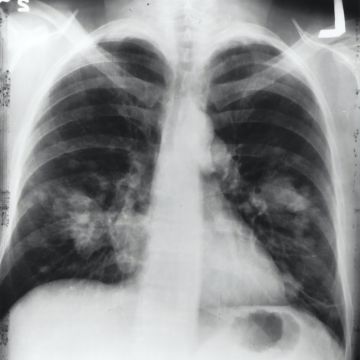

Chronische longziekten – zoals COPD en bronchitis

Kanker – verhoogd risico op long-, keel-, en blaaskanker